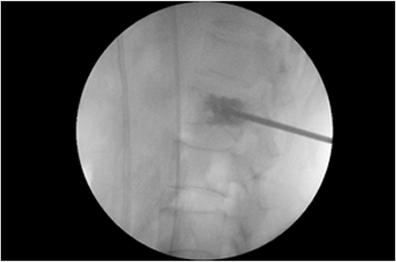

경막외 풍선확장 신경성형술 시술 방법

시술방법

1mm 정도의 조절 가능한 특수 카테터와 주사 바늘을척추 병변 부위에 접근한 후 신경 압박 부위까지

정확히 위치시켜, 부어오른 신경을 실시간으로 보면서 압박을 완화하거나 약물을 주입합니다.